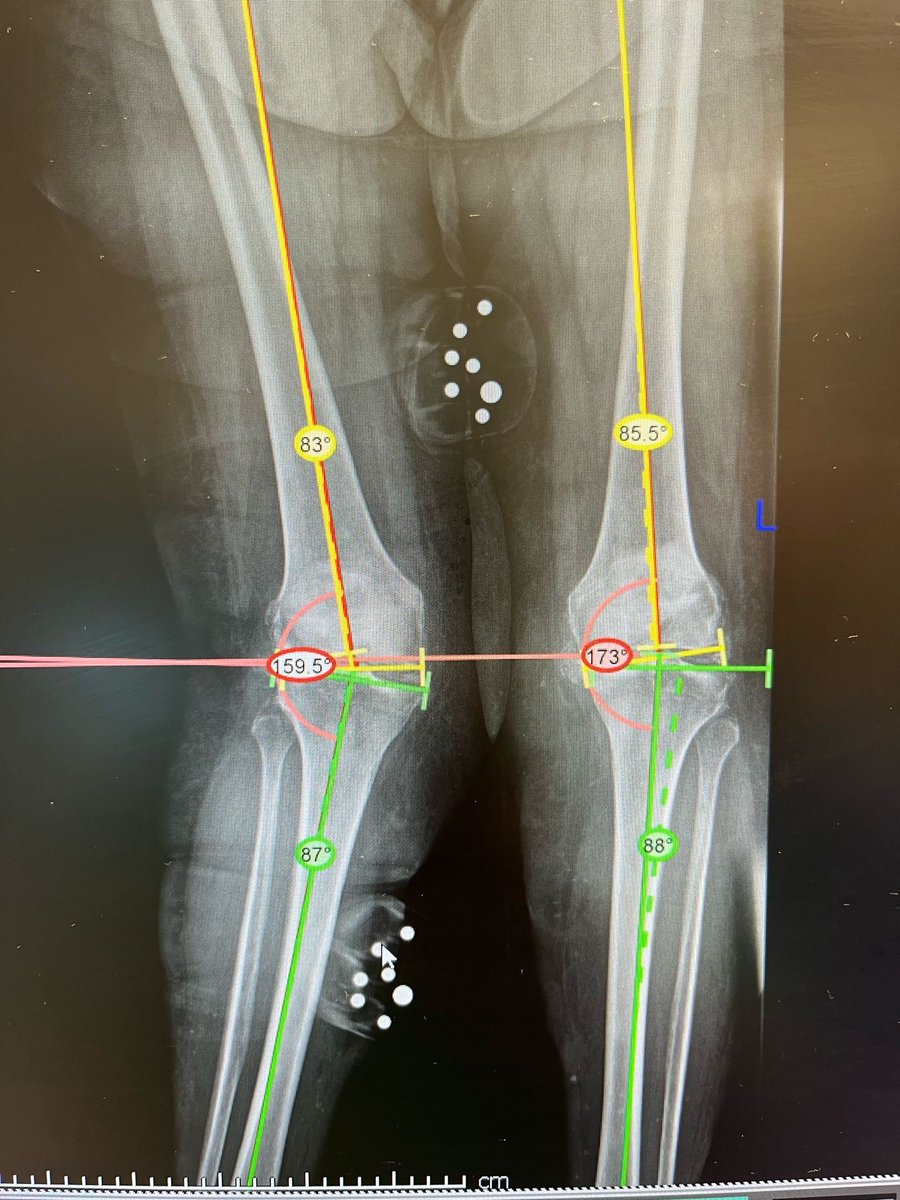

We welcome our first 'Bangor Zimmer Biomet hip and robotic knee fellow' Dr. Nishu Gupta to our unit. Week 2 - getting to know the ROSA. 37+ high BMI patient and 21.5-degree valgus deformity! Careful planning and perfect execution with the robot = great outcome! @kathryn_h_c